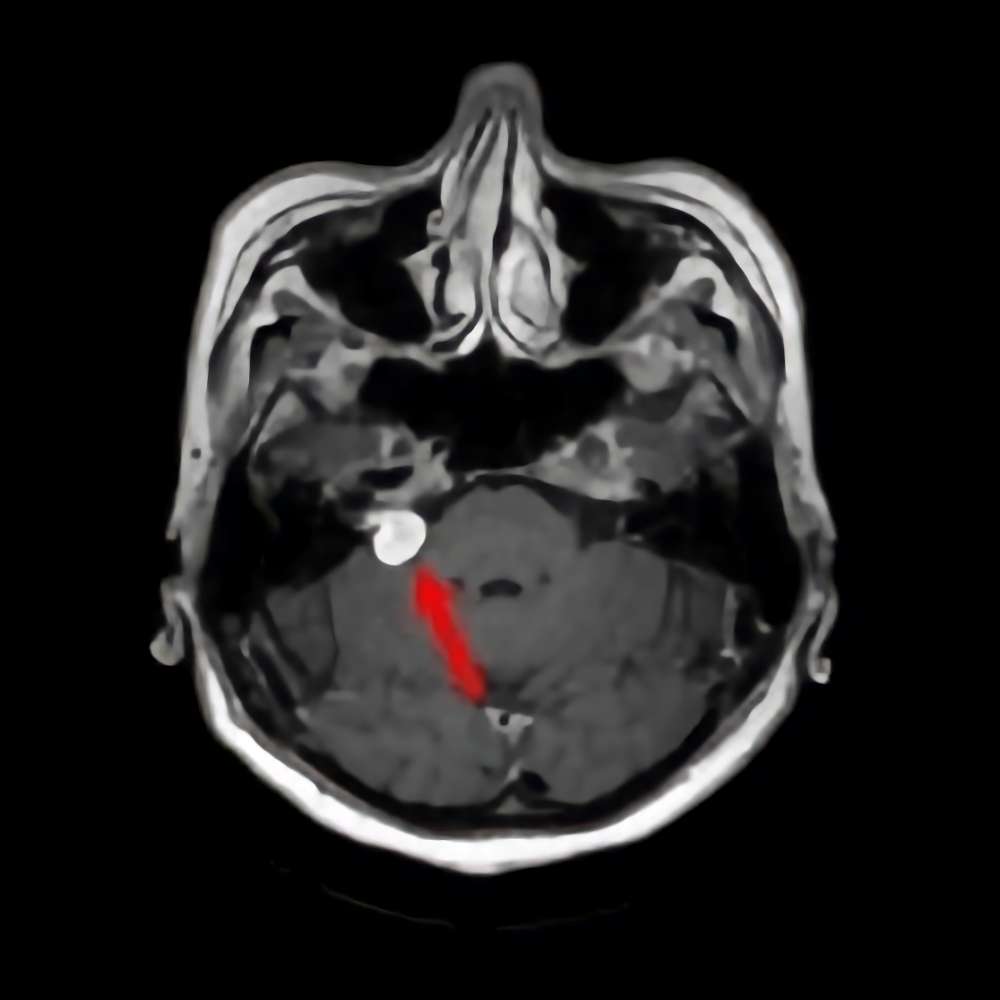

No.’21_27 手術前1

No.’21_27 手術前2